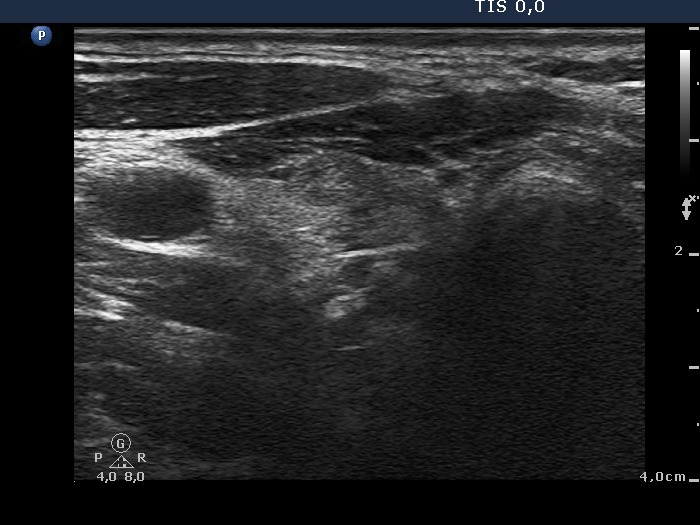

Right lobe, longitudinal scan

Lower part of the right lobe, transverse scan. There is a small hypoechogenic lesion with hyperechogenic figures.